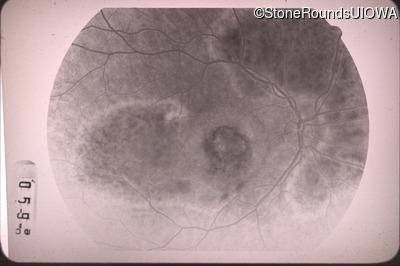

Fluorescein Angiography - Right - 20/100 -1

Exemplar